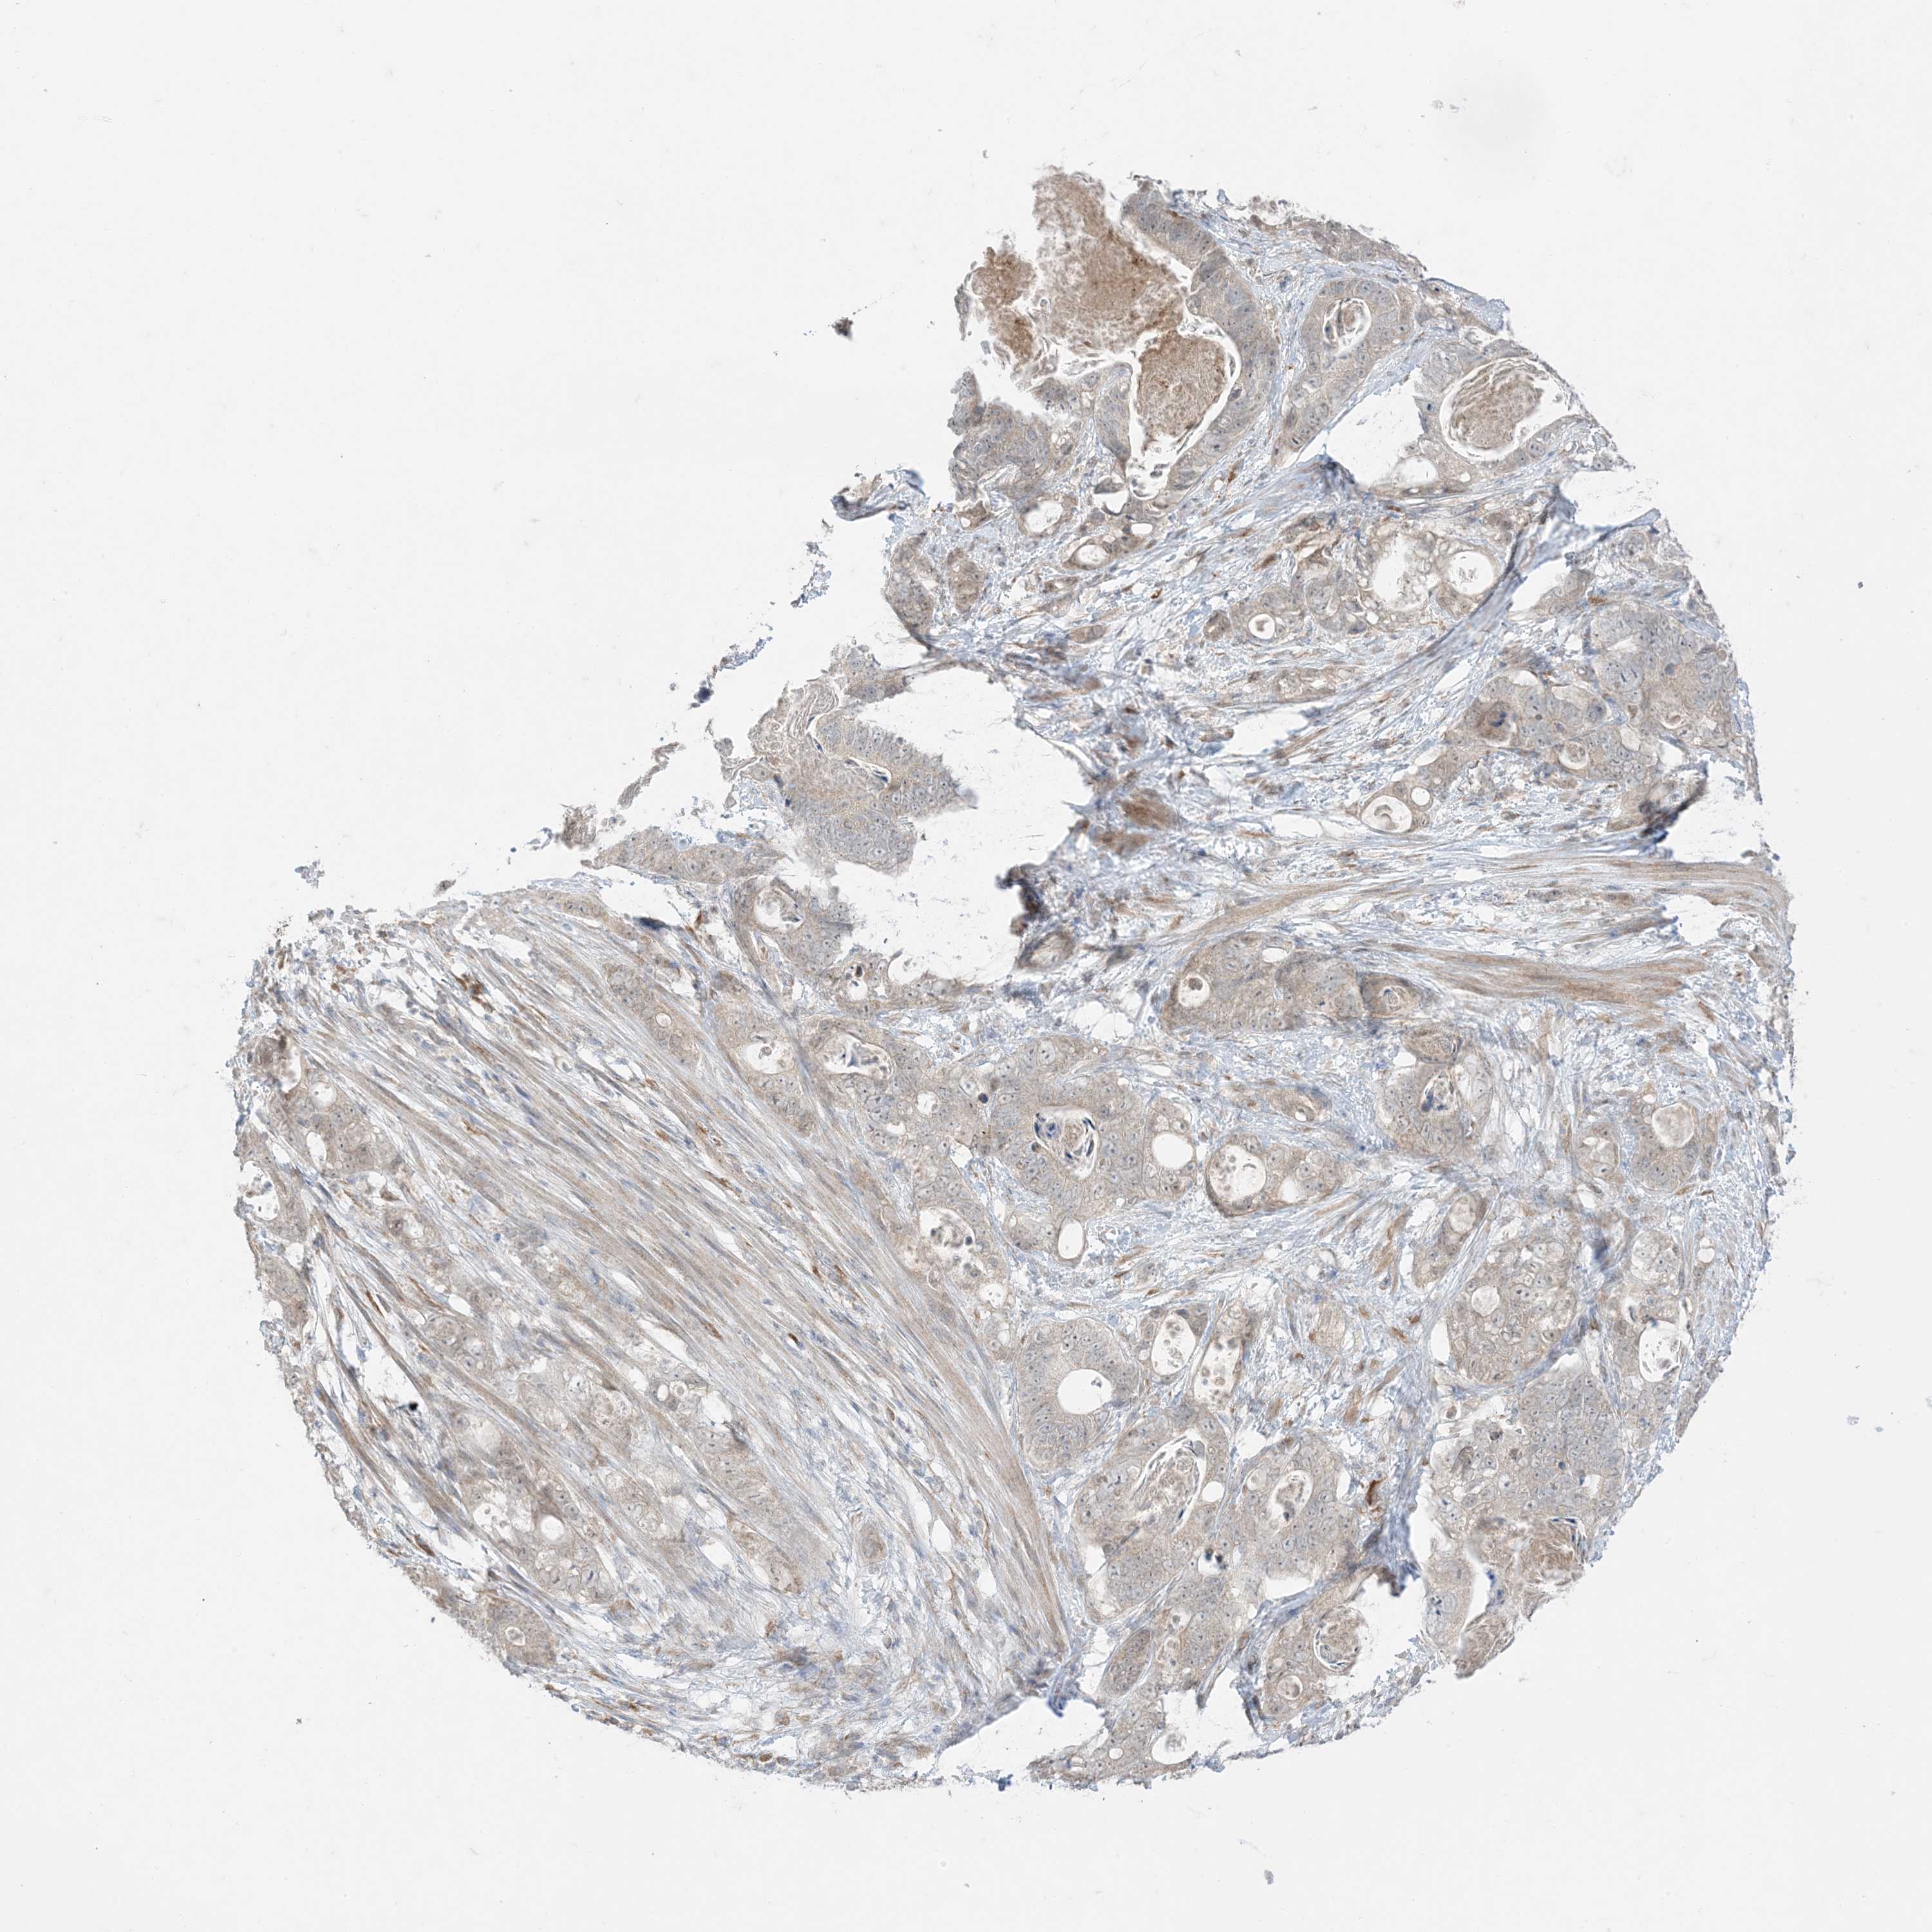

STOMACH CANCER - Protein expressioni

A mouse-over function shows sample information and annotation data. Click on an image to view it in a full screen mode. Samples can be filtered based on level of antibody staining by selecting one or several of the following categories: high, medium, low and not detected. The assay and annotation is described here.

Antibody stainingi

Antibody staining in the annotated cell types in the current human tissue is reported as not detected, low, medium, or high, based on conventional immunohistochemistry profiling in selected tissues. This score is based on the combination of the staining intensity and fraction of stained cells.

Each image is clickable and will lead to virtual microscopy that enables deeper exploration of all samples and also displays staining intensity scores, fraction scores and subcellular localization as well as patient and tissue information for each sample.

Staining

High

Medium

Low

Not detected

Intensity

Strong

Moderate

Weak

Negative

Quantity

>75%

75%-25%

<25%

None

Location

Nuclear

Cytoplasmic/membranous

Cytoplasmic/membranous,nuclear

Adenocarcinoma, High grade